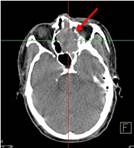

Ca lâm sàng 1: Bệnh nhân Vũ D.L., nam, 56 tuổi. Chẩn đoán: Non-Hodgkin Lymphoma , GPB: WF7.

Hình PET/CT toàn thân thấy tổn thương hạch ở nhiều vị trí: vùng cổ, trung thất, hố nách, ổ bụng, bẹn (các mũi tên)